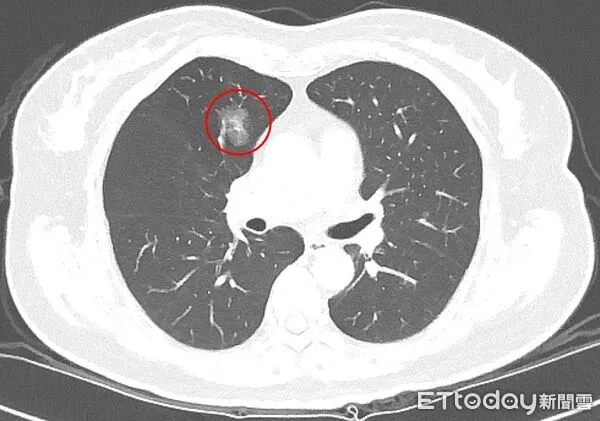

▲極早期的微小肺部結節。若醫師難以判讀,應定期追蹤。(圖/台北慈院提供)

吳智偉提醒,早期的結節因體積小,部分甚至無法進行切片,目前多以0.8公分作為基本判斷門檻;當影像一時難以判讀,更應規律追蹤,若後續擴大或特徵改變,再與醫師討論是否進一步治療。